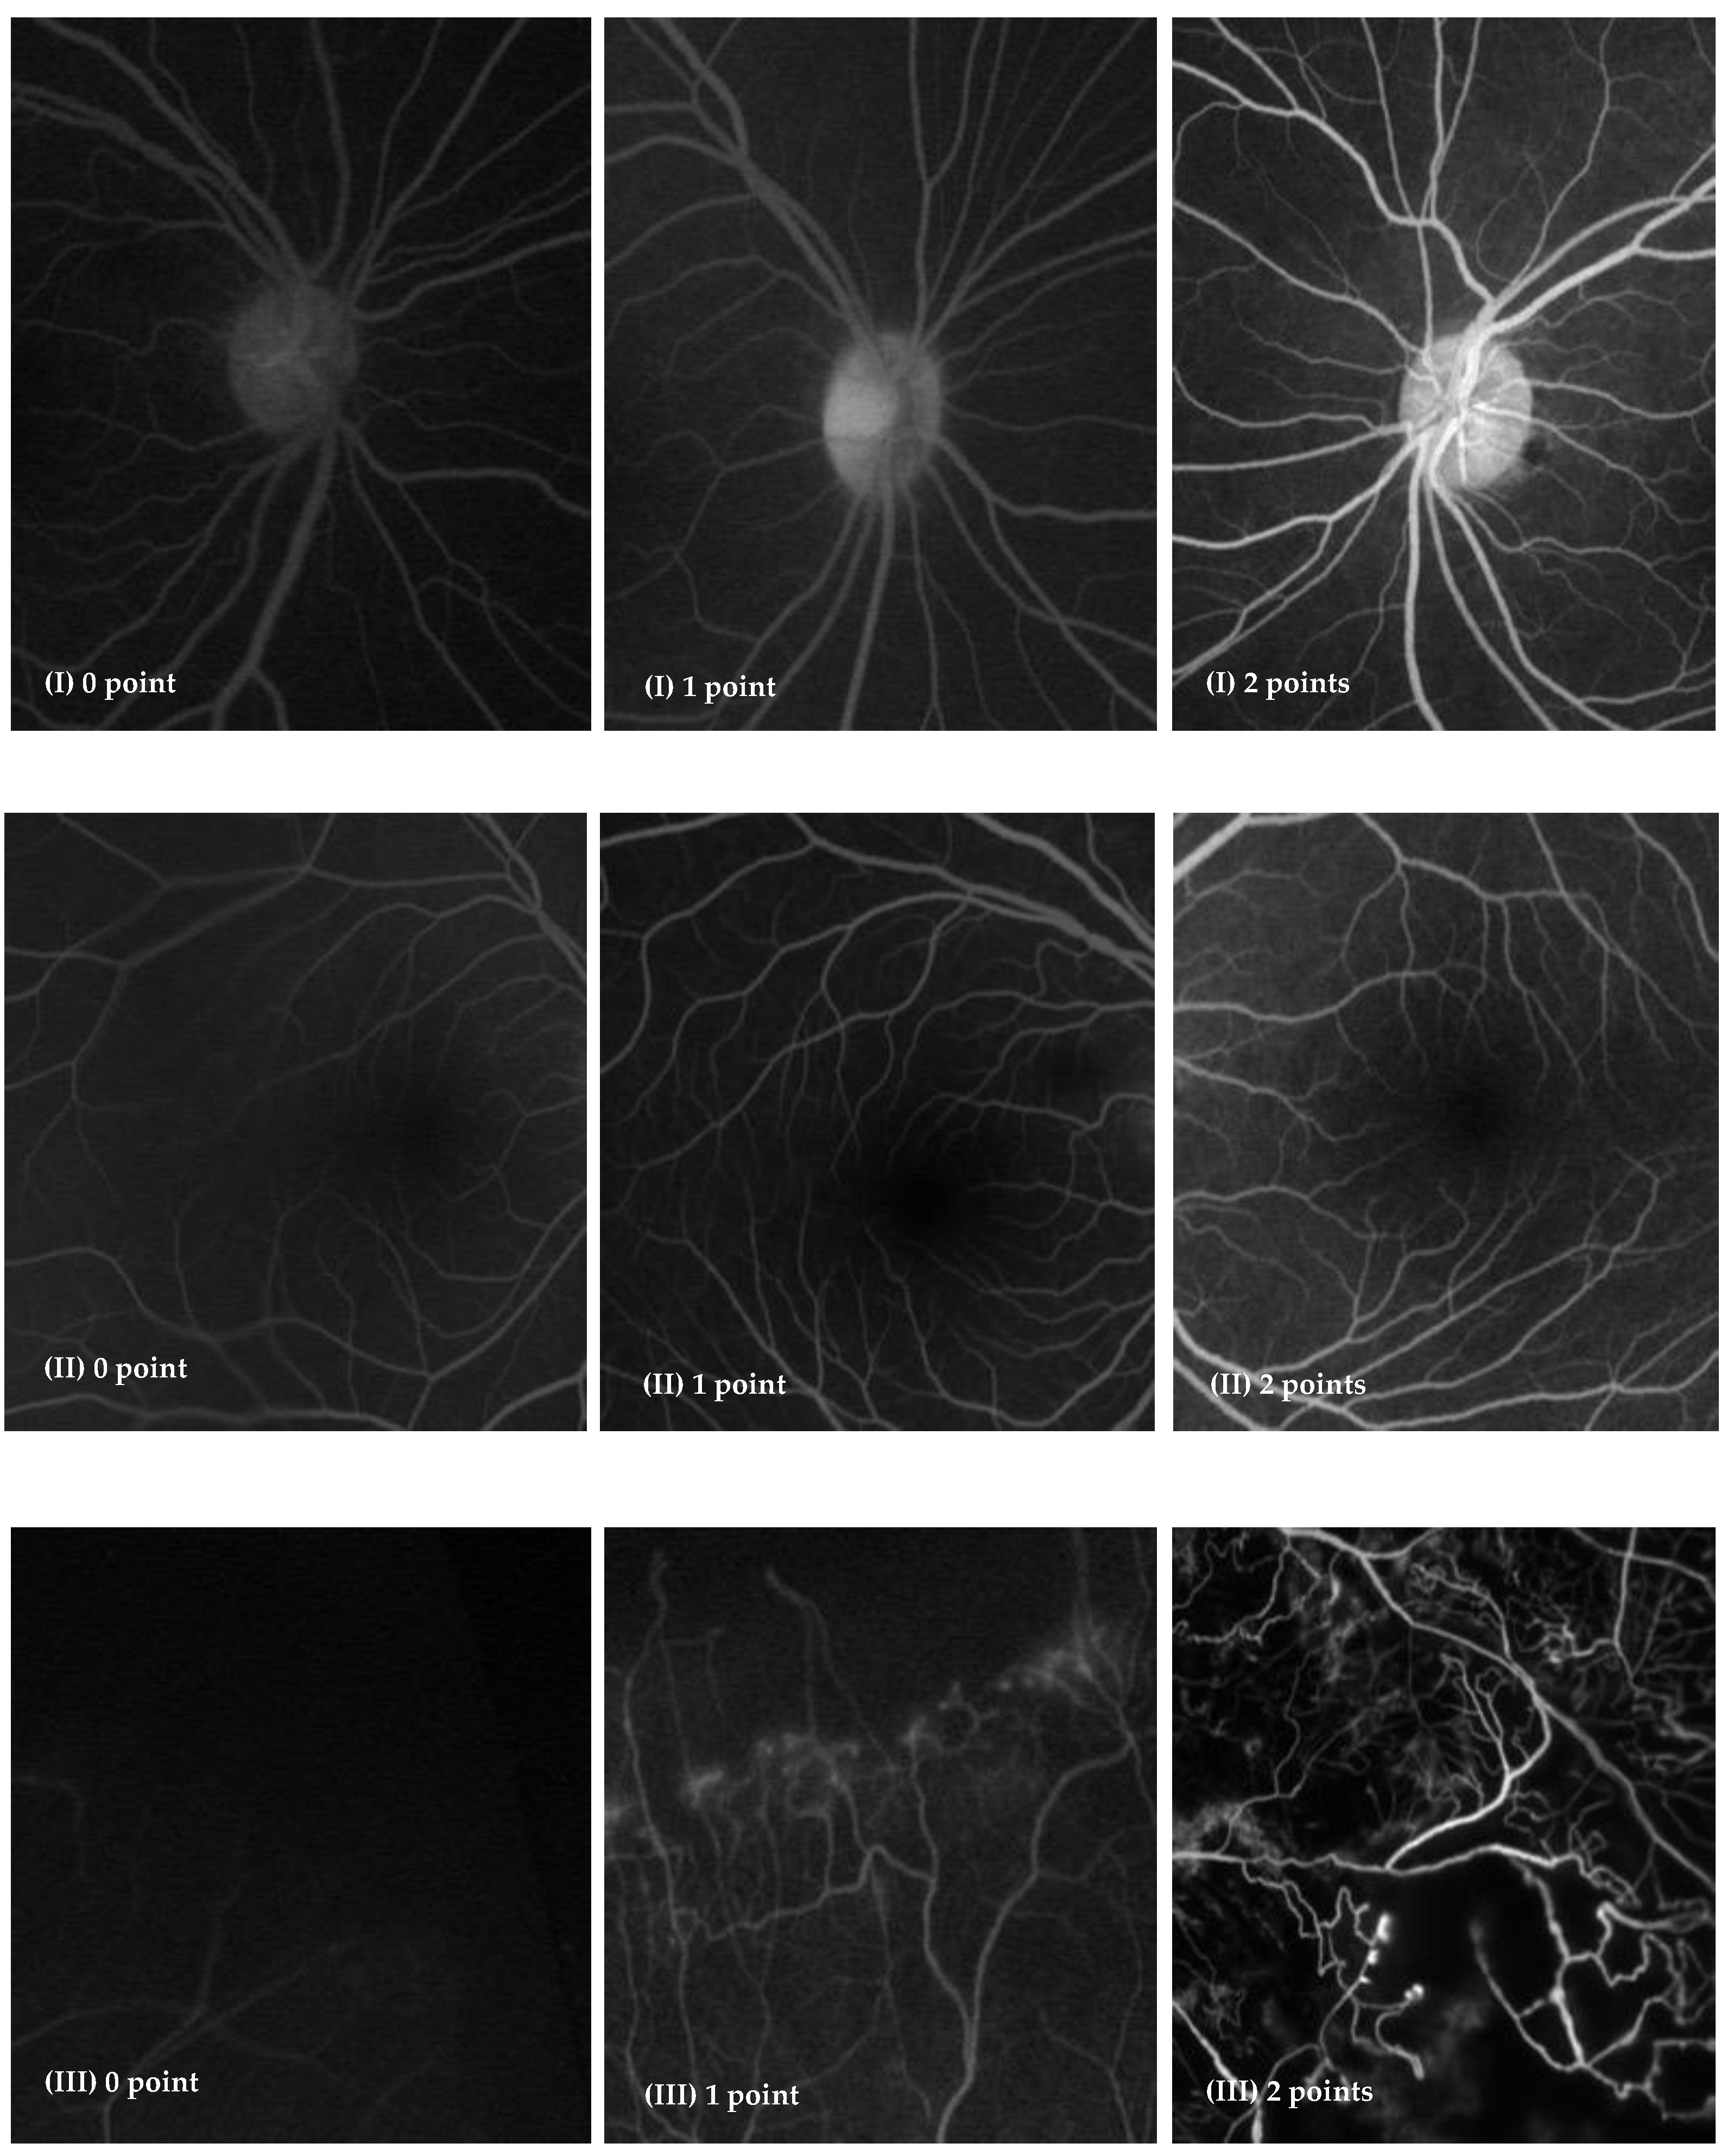

| I. Visualization of branch retinal vessels visualization | 36(100%) | 36 (100%) | 1.000 |

| II. Visualization of foveal avascular zone | 32 (100%) | 32 (100%) | |

| III. Identification of clinically important findings | 28 (100%) | 28 (100%) | |

| Microaneurysms | 4 (100%) | 4 (100%) | |

| Neovascularization | 4 (100%) | 4 (100%) | |

| Leakage | 9 (100%) | 9 (100%) | |

| Significant nonperfusion | 11 (100%) | 11 (100%) |